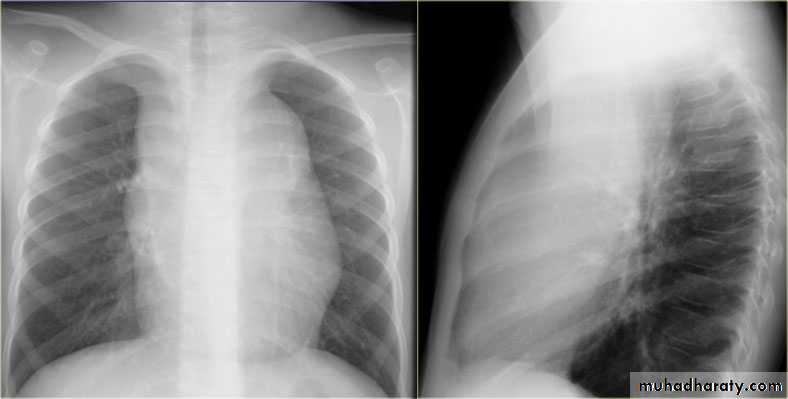

Normal chest XR PA & lateral view

Look carefully on both diaphragmatic cruse costo & cardio phrenic angles

Don't forget to use rib in asses lung Zones

1,2,3 .presentation4.normal chest film ( PA ) view

5.PA vs AP view

6.lateral film position

8.normal chest XR PA & lat. view